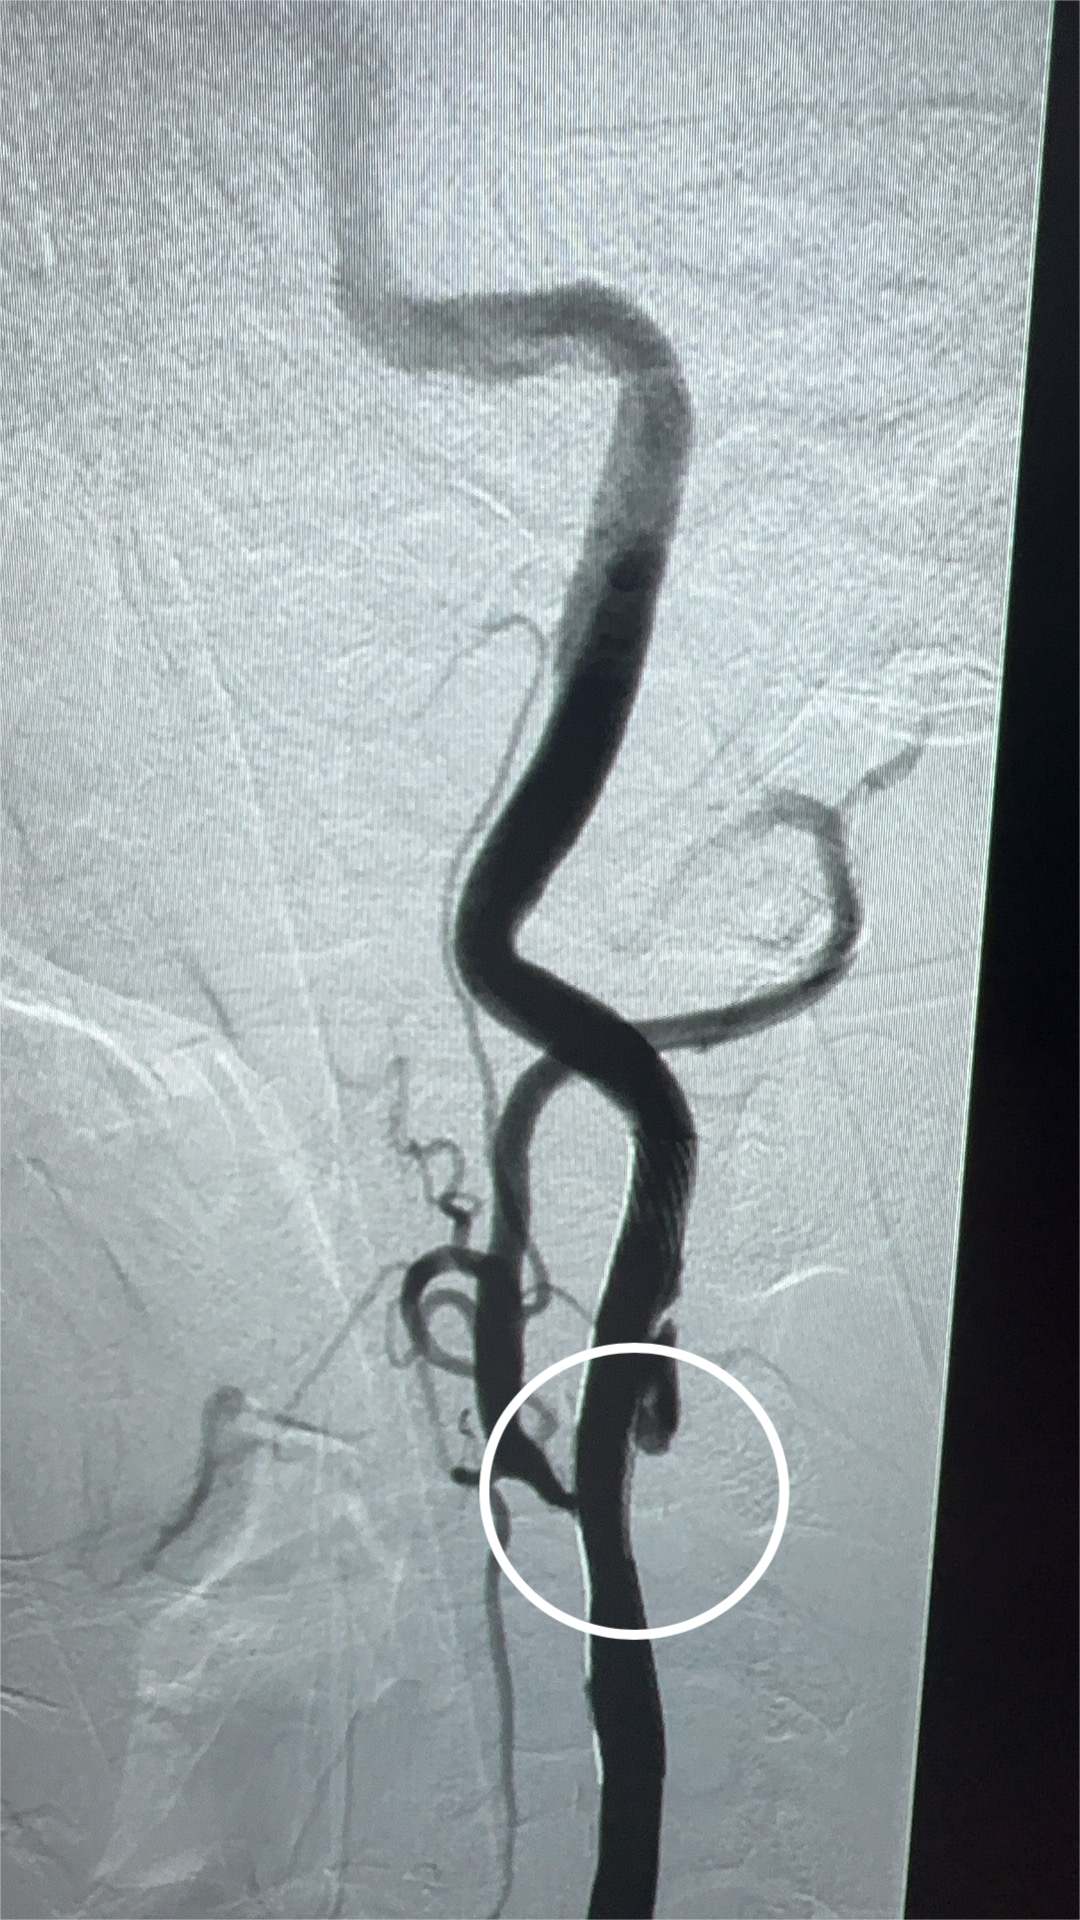

術(shù)前(左)、術(shù)后(右)的血管造影檢查

在麻醉科、介入室、放射科及電生理團(tuán)隊(duì)的通力合作下,陳大爺如期進(jìn)行了介入手術(shù)。術(shù)后,陳大爺恢復(fù)良好,無手術(shù)并發(fā)癥,術(shù)后3天就出院了,頭暈、眼前黑朦癥狀再未發(fā)生,自訴頭腦也比以前清醒了。復(fù)診時(shí),陳大爺特意送上準(zhǔn)備已久的錦旗,對醫(yī)護(hù)團(tuán)隊(duì)的精心治療及細(xì)致護(hù)理表示感謝。